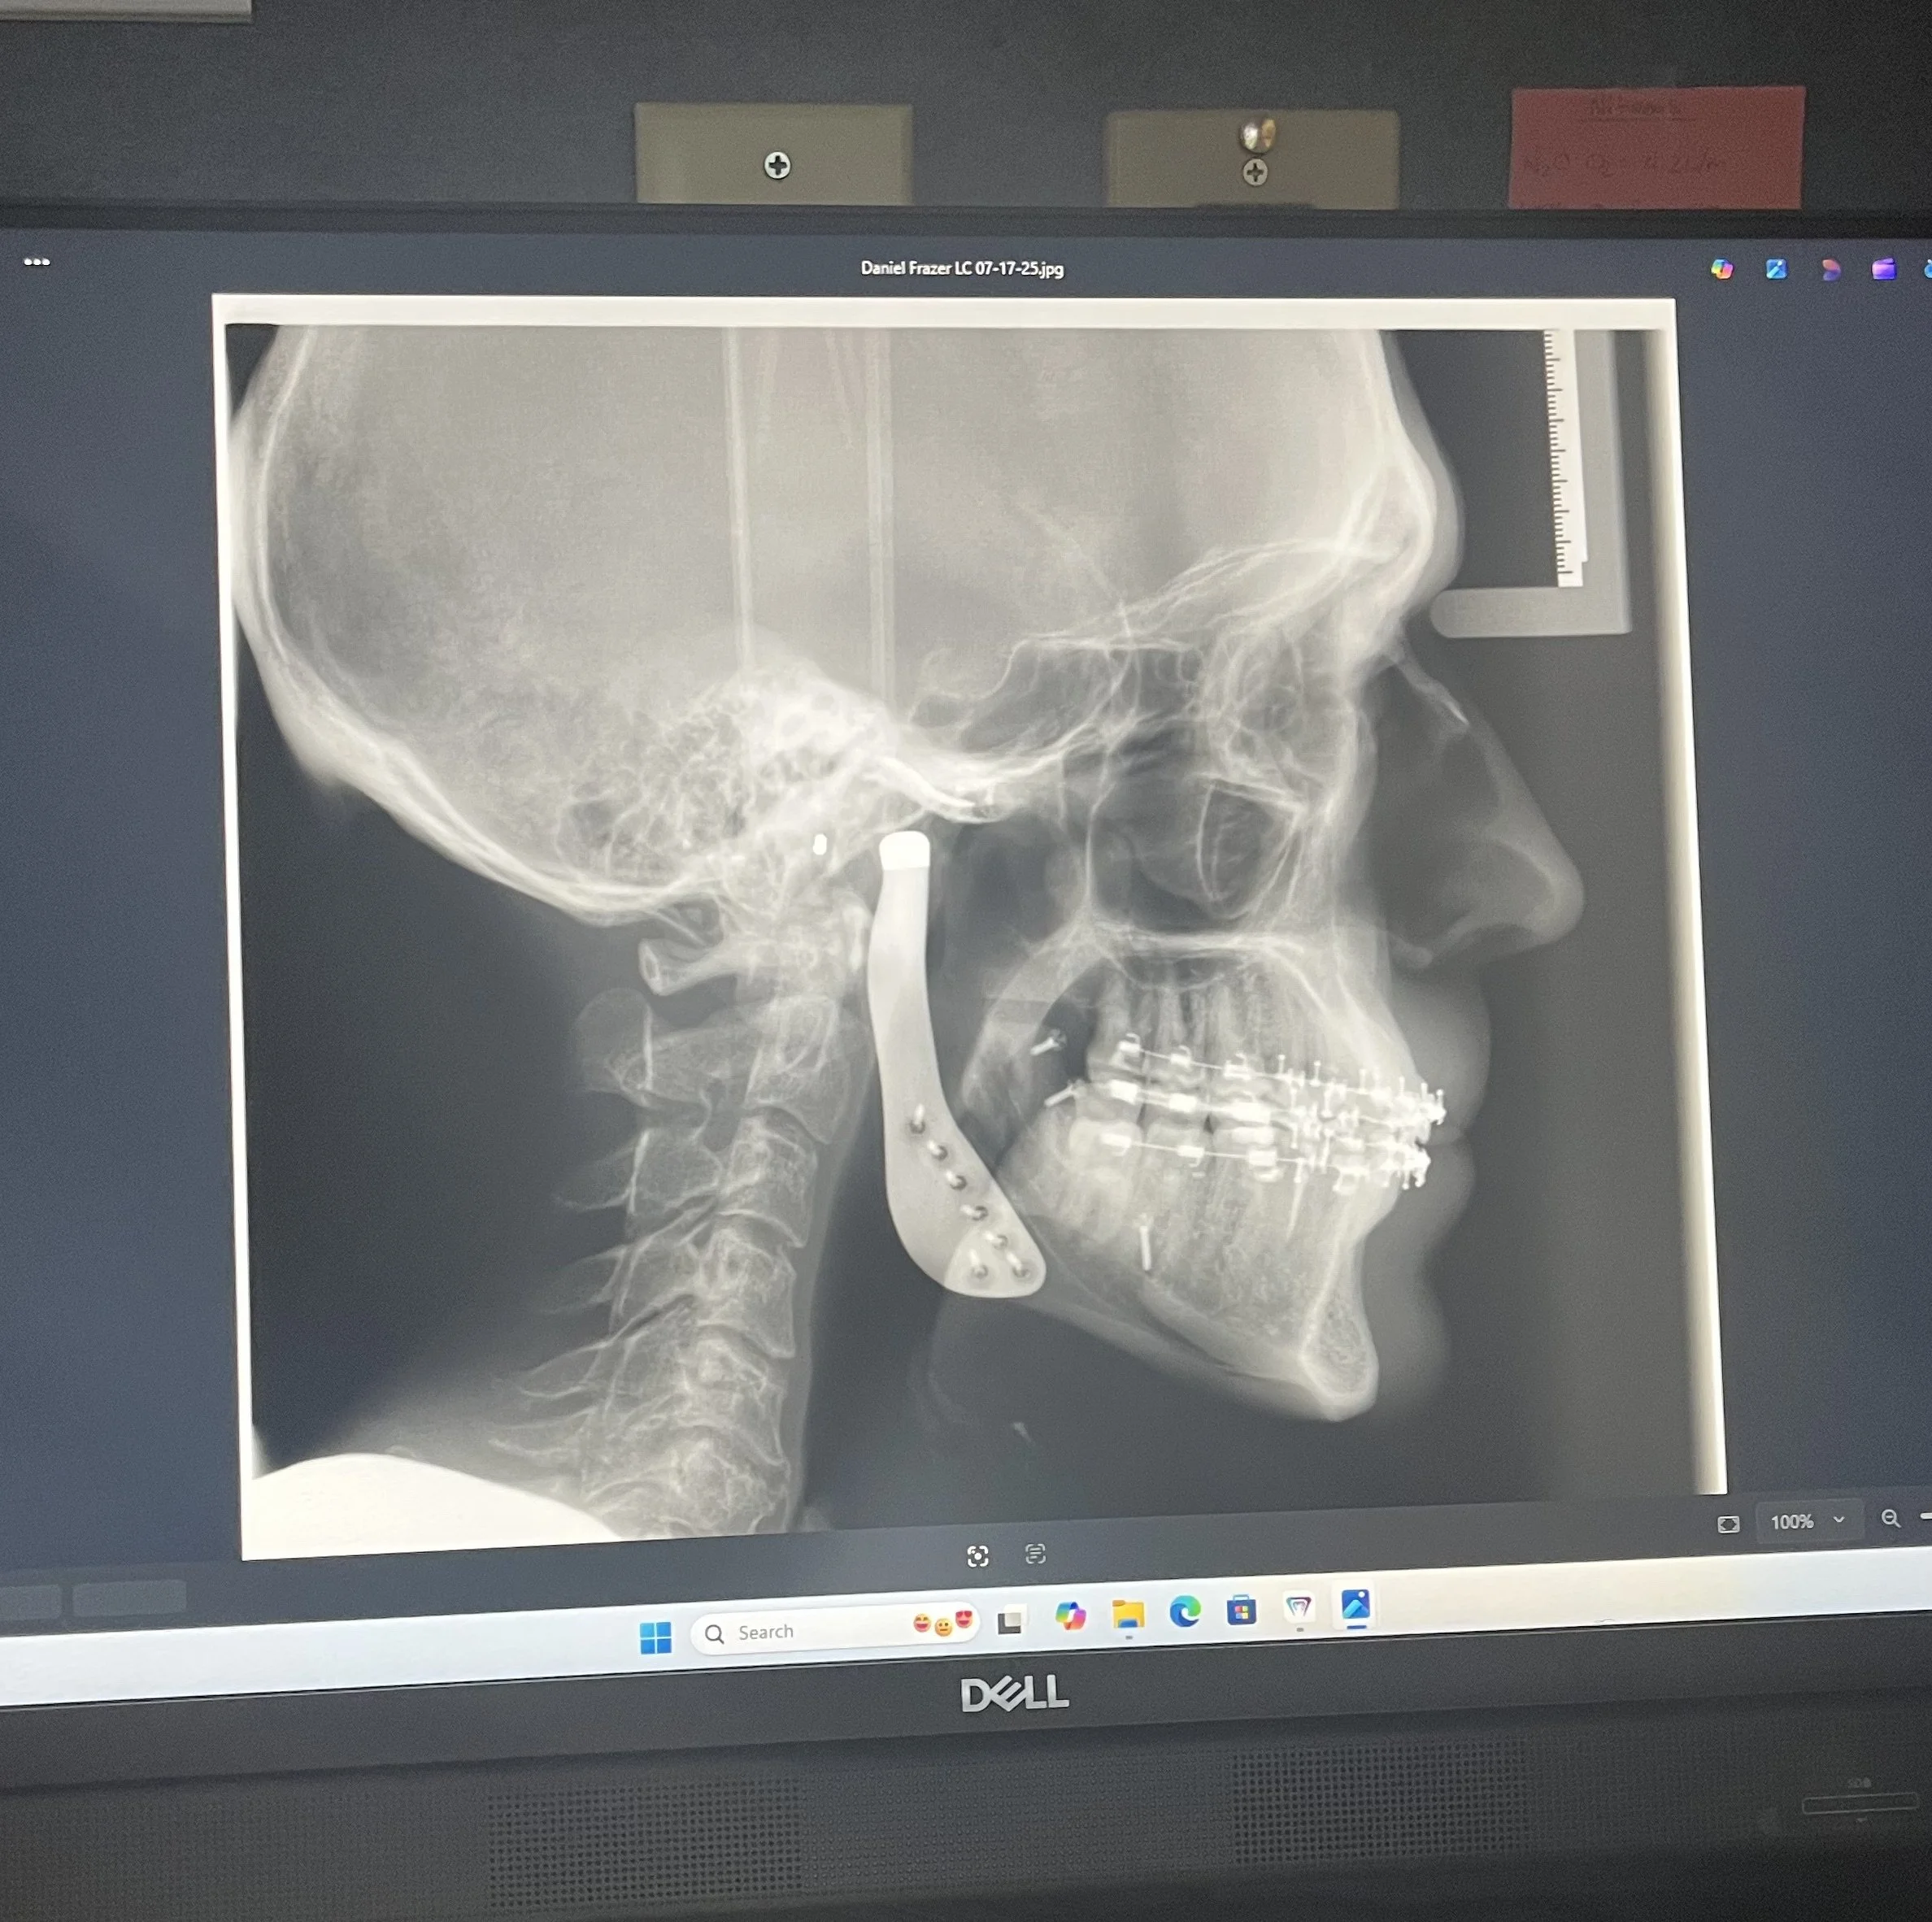

Pre-surgery rituals followed: blood pressure, body weight, confirmation of the procedure, and a collection of wristbands — red for “Allergy,” yellow for “Fall Risk,” and the usual hospital ID tags. My wife grilled the anesthesiologist, who graciously obliged her questions. Then Dr. Nelson, my surgeon, appeared, carrying a worn leather bag passed down from his father. Inside: a model of my teeth and his surgery checklist.

Moments later, I said goodbye to my wife and was wheeled into the OR. I briefly met the second surgeon before drifting off. Six hours passed in an instant. I woke up groggy, dazed, and — unexpectedly — in the ICU.

I didn’t know I’d eventually need facial reconstructive surgery because of a benign tumor impacting my jaw’s functioning. I simply wanted to feel good, keep up with my boys, and manage stress in healthy ways. That long arc of preparation turned out to mean everything when faced with this unlucky hand.